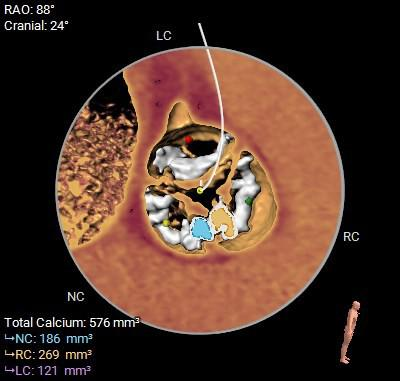

在完成术前CT扫描后发现,李阿姨入路腹主动脉严重扭曲、横位心、右冠窦无冠窦钙化融合且冠脉开口位置相对较低,左冠瓣叶冗长,术中冠脉闭塞风险高,这些不利因素均会明显增加手术的难度和风险。为此,医院迅速启动多学科协作机制,由医务处牵头,联合心血管科、麻醉科、重症医学科、血管外科、胸外科等专家团队展开会诊。经过反复讨论,专家团队最终决定采用国际先进的治疗方案一一经导管主动脉瓣置换术(TAVR)。这种微创手术无需开胸,只需通过血管穿刺即可完成瓣膜置换,极大降低了手术风险。为确保万无一失,心血管科团队还通过线上会议邀请国内知名专家对病例进行远程讨论,制定了精细化手术方案,包括入路解决方案、冠脉保护策略、术中应急措施以及术后康复计划。

▲主动脉根部测量

患者病理特点

1. 冠脉高风险:三窦三叶式主动脉瓣,右无之间钙化融合,钙化分布不均。右无融合脊会把瓣架往左冠脉开口方向推挤,并且左冠瓣叶相对冗长,大大增加了冠脉阻挡的风险。

2. 腹主入路折角:双侧入路血管走形良好,整体入路血管条件一般,腹主动脉可见扭曲,经过测量33cm可以正好通过迂曲部位,也提前备好45cm长鞘,以防血管损伤。

3. 瓣膜通过性:由于横位心及大弯侧有融合脊形成台阶,瓣膜输送器通过会受影响,预备同侧snare圈套,以防无法通过。